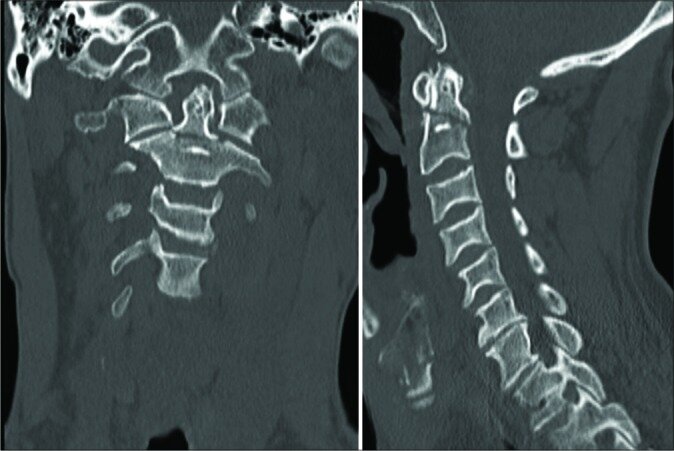

Case description: A 64-year-old neurologically intact patient with a type II odontoid fracture secondary to trauma underwent anterior odontoid screw fixation without any intraoperative complications. He tolerated the procedure well, and postoperative imaging demonstrated near anatomic correction of the fracture with satisfactory placement of the lag screw. Unfortunately, the patient was subsequently lost to follow up and he presented 7 months later for a routine outpatient computed tomography (CT) of the cervical spine, which demonstrated upward migration of the screw into the intracranial cavity abutting the medulla, with CT angiography of the neck also confirming the screw lying between the two vertebral arteries. Magnetic resonance imaging of the cervical spine also demonstrated the odontoid screw lying within close proximity to the ventral cervicomedullary junction, marginating the left vertebral artery. Subsequently, the patient was managed with removal of the odontoid screw and posterior cervical arthrodesis and instrumented fusion.